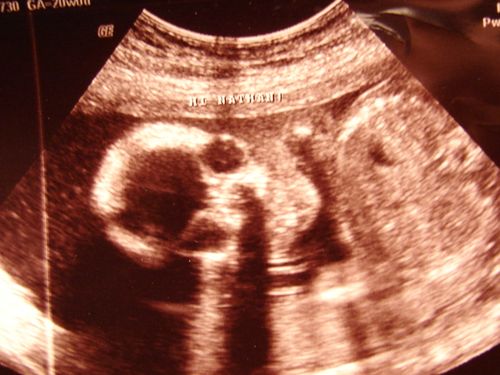

My little baby boy is looking healthy and growing so fast! His approximate weight is 13.5 ounces and he is quite flexible – at one point during the sonogram, he was seen tapping his foot on top of his little head! Nathan and Will got quite a kick out of that. The sonographer was very nice and even printed each of them their very own personalized photo that read "Hi Nathan" and "Hi William", complete with a great view of baby's head.

We did get some really good looks at him, though, including a look at his spine, fingers, toes, and lips, as well as his brain and and most of his vital organs that have already formed. His heart rate was 154 beats per minute.

Face view.